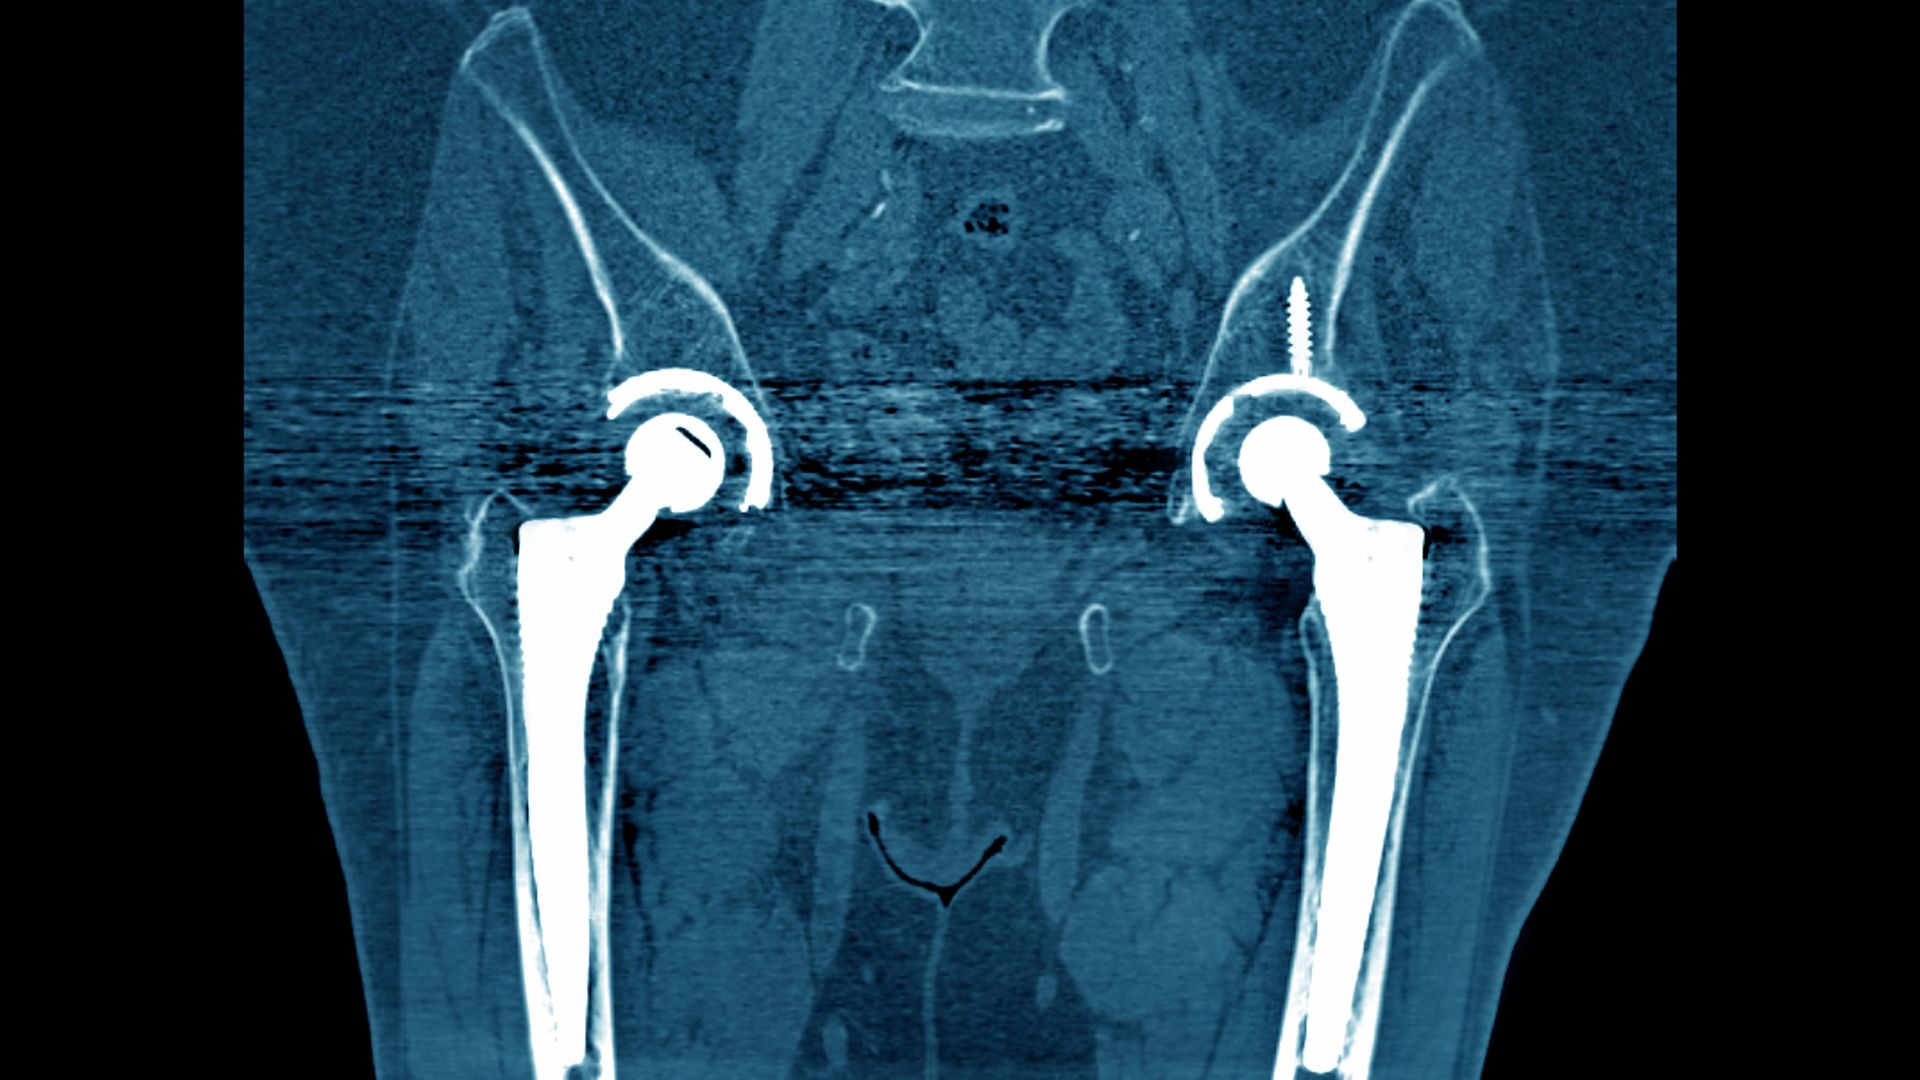

Johnson & Johnson plans on paying out $1 billion to settle almost all patient lawsuits involving its all-metal hip implants, although the health care giant still faces other lawsuits related to its other hip implants, Bloomberg reports.

The big picture: The hip settlements are just the tip of the legal iceberg for J&J, which also is facing high-profile litigation over its baby powder, pelvic mesh implants and opioids.